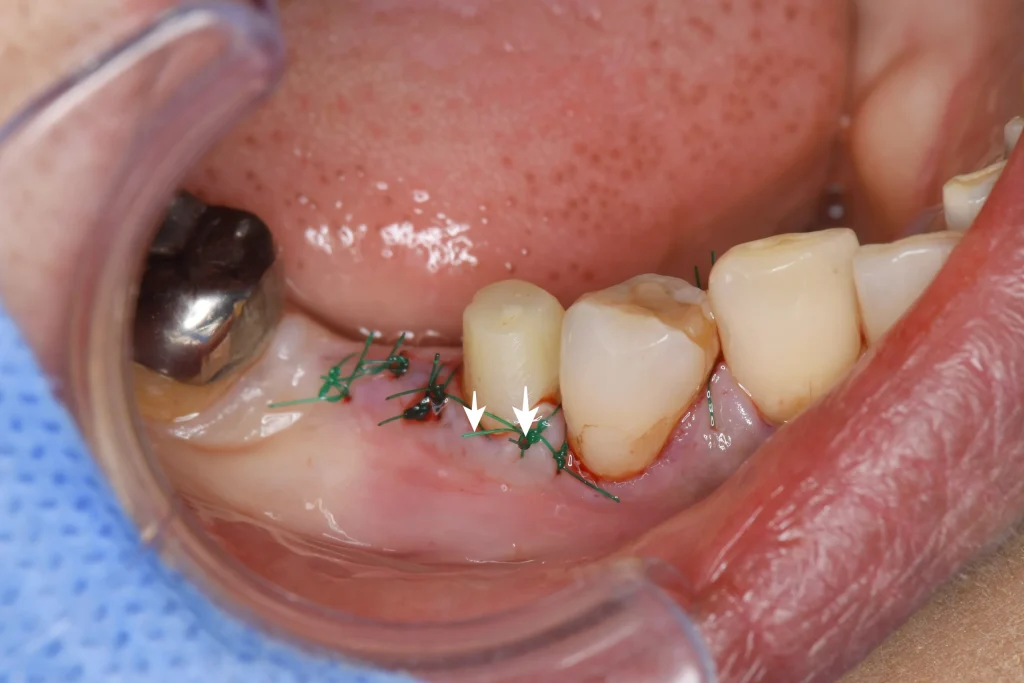

歯茎を捲り、歯を支えている骨を一部削り、それに合わせて白矢印の方向に歯茎を下げました。

そうすることで、被せ物をさせる健康な歯質を露出させることができますので、破折や脱離に抵抗することができるようになります。

| 歯冠延長術と歯槽骨整形の後、セラミックブリッジで治療(60代女性) |

| 右下の銀歯の下の虫歯を治療し、歯冠延長術を行いその後ジルコニアブリッジにて補綴処置を行なった。 |